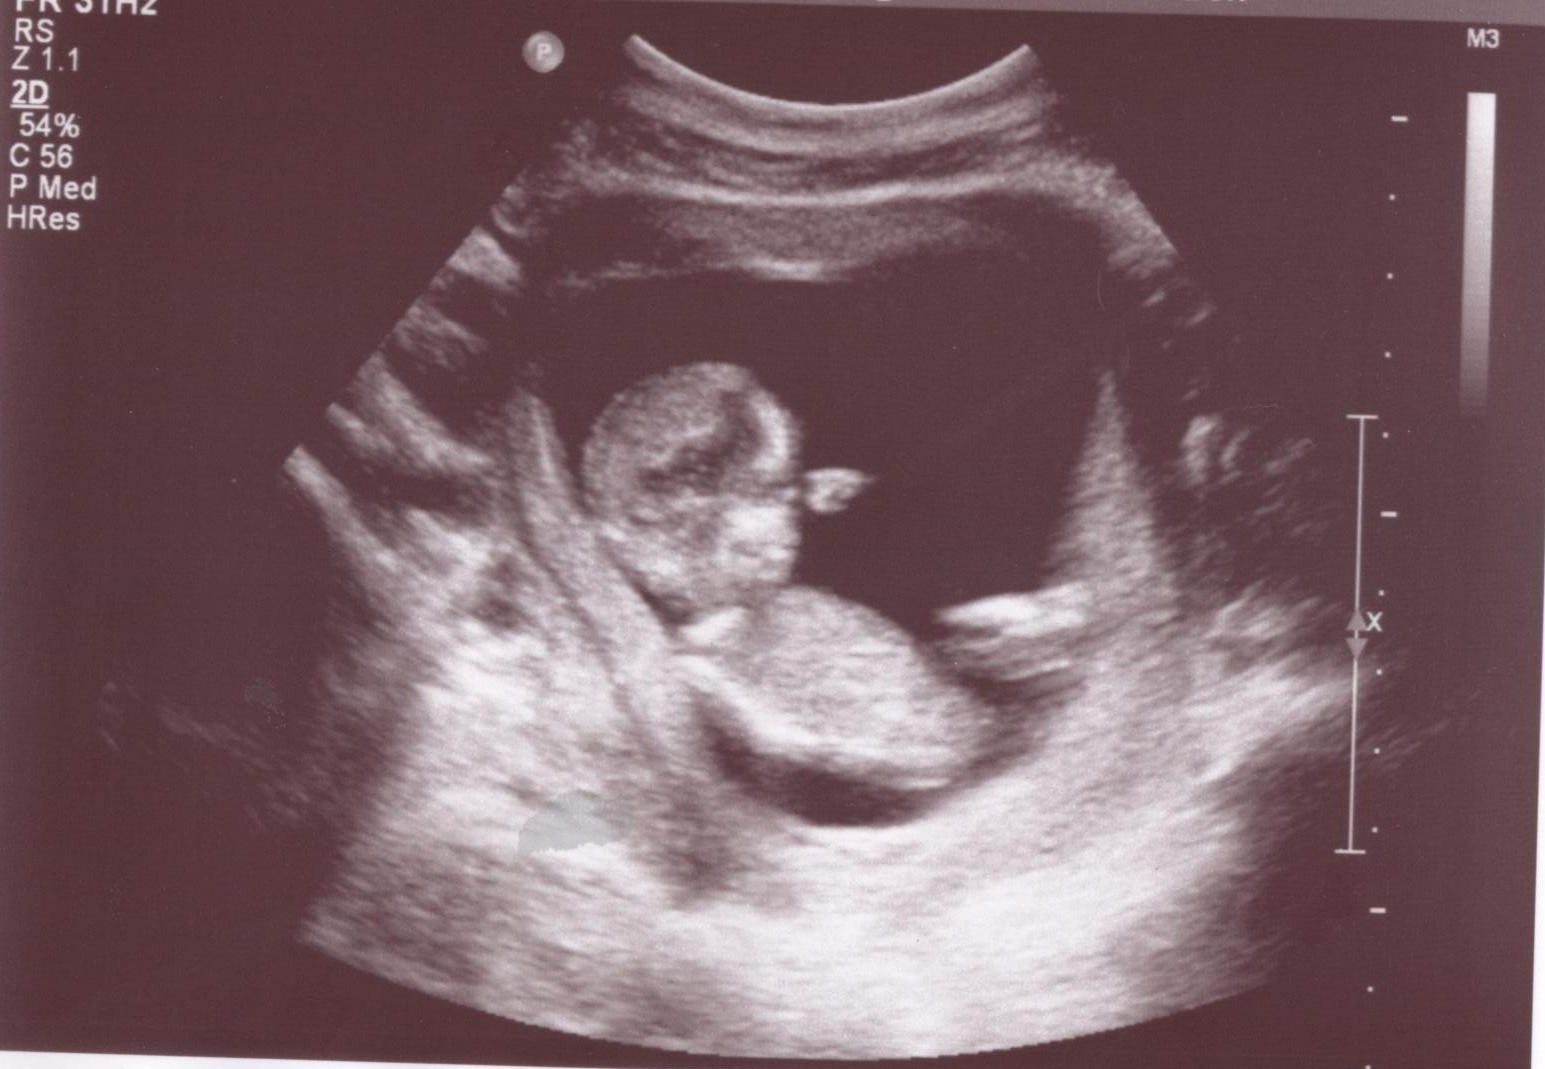

As I lay on the table any thoughts of sickness vanished as soon as I saw our precious little bean. The poor little baby was not being very cooperative for our sonographer that day as s/he was fast asleep. I guess mommy kept him/her up all night with trips to the bathroom. The sonographer apologised but in order to get a specific picture she was going to have to press down hard on my belly with the ultrasound wand. At this point I could feel the litre of water gurgling around in my stomach looking for an escape..and in a non-traditional route.

After a few minutes of her prodding and me trying my best not to vomit, the baby repositioned him/herself and extended his/her arm in front of the mouth almost as if to block a yawn ''are we done yet so I can get back to sleep?'' At this point in the pregnancy, the baby was measuring right on target at around 3inches. it is amazing to think that something so small can already be making such a huge impact in my life. I wish I could see my little bean every single day.